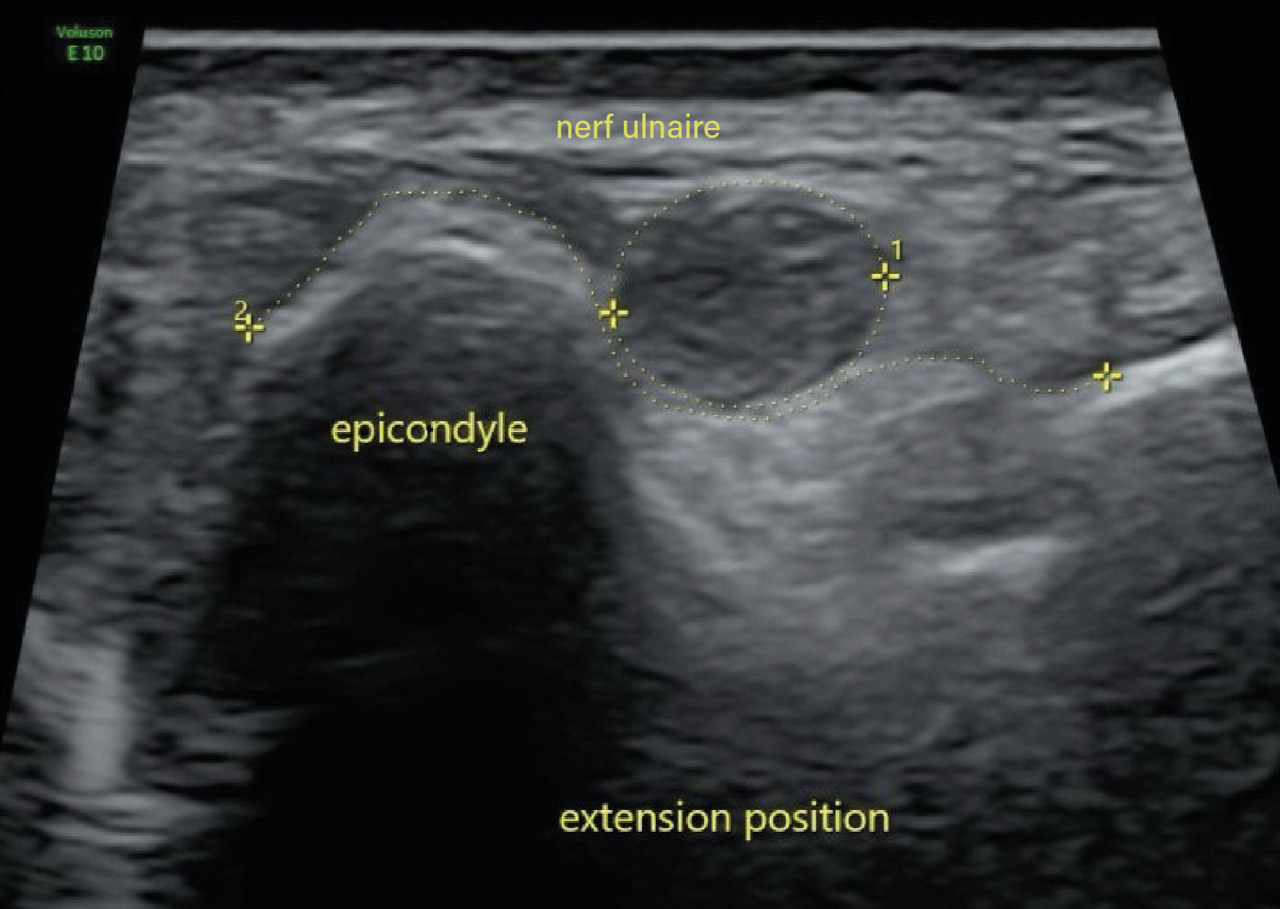

Deux ans après le premier épisode, il reconsulte pour le même motif. Un nouvel EMG révèle un ralentissement de la vitesse de conduction du nerf ulnaire droit au niveau du coude. Une échographie dynamique du coude met en évidence un gonflement fusiforme du nerf ulnaire dans la gouttière cubitale ainsi qu’une luxation du nerf ulnaire au-delà de la tubérosité condylienne lors de la flexion de l’avant-bras sur le bras (fig. 1 et 2). Une transposition cubitale est effectuée (fig. 3) permettant la disparition des symptômes en quelques semaines.

Le choix du traitement est dicté par la sévérité des symptômes moteurs et sensitifs. Un traitement conservateur peut être envisagé en premier lieu, en l’absence de signe moteur ou sensitif. Les flexions prolongées du coude sont à éviter, avec parfois la nécessité d’un recours aux ­attelles d’extension nocturnes à 30 °. Dans les autres cas, le traitement est chirurgical et consiste en une transposition antérieure du nerf cubital.